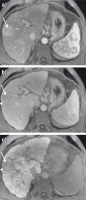

Abbildung 2a-c: MRT-KM-Anfärbeverhalten bei Fokaler Nodulärer Hyperplasie (FNH): (a) In dem T1-gewichteten Bild ohne Kontrastmittel ist keine fokale Leberläsion zu erkennen, da FNHs meistens ähnliche Signalintensitäten (= Helligkeit) wie das umgebende Lebergewebe aufweisen. (b) Nach KM-Gabe zeigen die 2 nebeneinanderliegenden FNHs ein starkes KM-Enhancement in der arteriellen Phase und sind gut detektierbar. (c) 20 Minuten nach Gabe von Gadoxetat (Primovist®) zeigen die 2 nebeneinanderliegenden FNHs eine ähnliche KM-Aufnahme wie das umgebende Lebergewebe. Es demarkieren sich nun auch die charakteristischen (dunklen) Narben. Dies sind sichere radiologische Merkmale für die Diagnoseerstellung von FNHs.